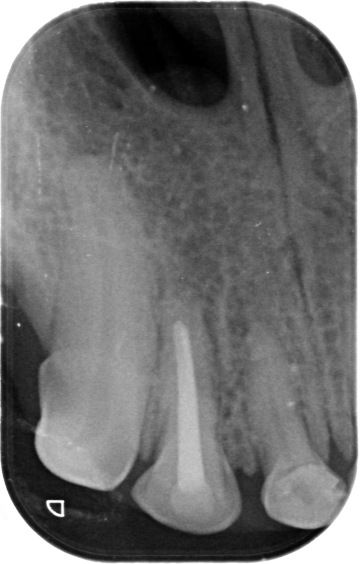

Diagnostics - intraoral X-ray

The x-ray of your pet's teeth is similar to that of humans. An x-ray machine using a small amount of radiation is used to view the inside of your dog's teeth and those areas below the gum line that are hidden. Unlike humans, animals must be under general anesthesia for a dental X-ray, as it is practically impossible to get them to hold the plate in their mouth and not bite into it. You can read more about the anesthesia itself and what it all entails here.

Animals just can't tell us when their teeth are sick and some never show that they are in pain. In many cases, an intraoral x-ray is the only way we can tell that your pet has a serious dental problem that can be treated and the discomfort alleviated.

It should be noted that quality dental treatment requires x-rays of the teeth. Without an x-ray of the teeth, it is practically impossible to assess the condition of the periodontium, and diseases that occur below the level of the gums are invisible to the human eye.